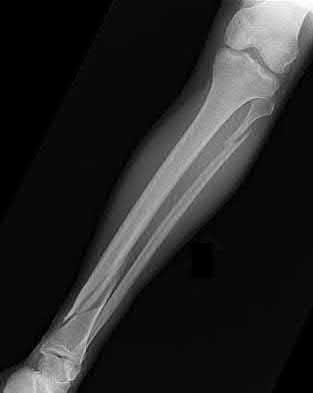

4. # After undergoing the treatment seen in Figure A, when should a patient be expected to safely operate the brakes of an automobile?

Corrent answer: 4

Figure A shows a patient after an open reduction and internal fixation of a bimalleolar ankle fracture.

Egol et al showed that by nine weeks, the total braking time of patients who had undergone fixation of a displaced right ankle fracture returns to the normal, baseline value.

Egol et al, also found that appropriate braking time returns at a point 6 weeks after initiation of weightbearing after treatment of lower extremity long bone and periarticular fractures, as examined with a driving simulator. No differences were seen in return of braking time between periarticular fractures and long bone injuries.